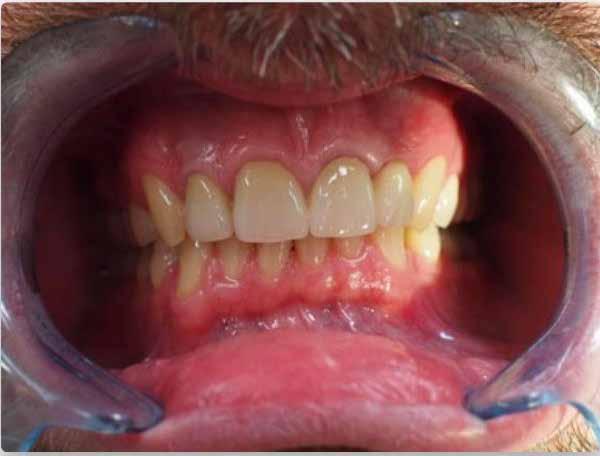

A CBCT-készülékek endodonciai alkalmazásának talán az az egyik legnagyobb előnye, hogy így olyan anatómiai struktúrák is láthatóvá válnak, amelyeket egyébként nem tudnánk detektálni panoráma, cephalo, vagy periapicalis felvételek segítségével. Mivel a CBCT-felvételek kiértékelése számítógép segítségével történik, így a felvételek vizsgálata során lehetőségünk van az adott területet több nézőpontból és több síkban is megvizsgálni. 2015 októberében egy korábban a rendelőnkben kezelt 55 éves férfi páciens azzal a céllal kereste fel ismét a rendelőnket, hogy másodvéleményt kérjen egy jobb felső kvadránsban található fogával kapcsolatban. Egy másik rendelőben történő vizsgálat során a panaszos fog törését vélelmezték és a fog eltávolítását javasolták, illetve arról is beszámolt, hogy az elmúlt hét során ezen a területen egy puha duzzanat is kialakult. A klinikai vizsgálat során a jobb felső első és második kisőrlő között (14–15) egy fluktuáló duzzanatot észleltünk az áthajlásban. Az 15-ös fog mesialis oldalán 12 mm mély tasakot szondáztunk. A páciens által hozott periapicalis felvételen a 15-ös fog gyökércsúcsának mesialis részén egy nagy kiterjedésű radiolucens elváltozás volt észlelhető (1. ábra). A saggitális síkban vizsgált CBCT-felvételen (Carestream CS 9000, Carestream Dental) a lézió valódi kiterjedése is láthatóvá vált (2. ábra). A megelőző endodonciai kezelések során csupán a bukkális csatorna került detektálásra és gyökértöméssel való ellátásra. Az axiális irányú CBCT-szeleteken egyértelműen látható volt az ellátatlan palatinális gyökércsatorna (3. ábra)

A buccalis csatornába üvegszálas csapot helyeztek, amely a csonkfelépítés elhorgonyzását biztosította. A pácienst arról is tájékoztattuk, hogy egy ferdén behelyezett fém parapulpális csap perforálta a fog koronáját és a csap vége eléri a parodonciumot. A páciens tájékoztatását követően az a döntés született, hogy célszerű lenne a palatinális gyökércsator-

na szelektív endodonciai kezelésének elvégzése. A páciens a javasolt kezelési tervet elfogadta.

Először kalcium-hidroxid alapú ideglenes gyógyszeres zárás került a palatinális csatornába (UltraCal XS, Ultradent Products; 4–5. ábra), amelyet 6 hét után a végleges gyökértömés elkészítése előtt eltávolítottunk. A gyökértömés elkészítése során meleg vertikális kondenzációs technikát alkalmaztunk. Radiológiai felvételen megfigyelhető volt, hogy a gyökértömő anyag egy laterális csatornán keresztül kis mennyiségben a periapicalis térbe extrudálódott (6. ábra). A 4 évvel később készített kontrollfelvételeken a lézió gyógyulása volt megfigyelhető (7–9. ábra). A vizsgálati eredmények és a kezelés kimenetele egyértelműen igazolta, hogy nem gyökérfraktúrával álltunk szemben, tehát a kezdeti diagnózis tévesnek bizonyult. Ez is azt erősíti, hogy korlátozott mennyiségben rendelkezésre álló adatok alapján nem lehet pontos diagnózist felállítani. Manapság szinte elengedhetetlen a CBCT-felvételek endodonciai beavatkozások során történő használata, feltéve, ha ezek elkészítése során az ALARA elv (as low as reasonably achievable) betartásra kerül.